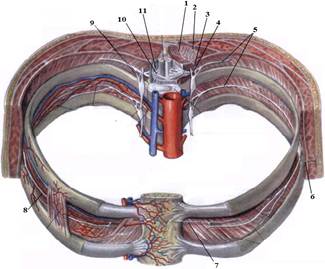

ТЕМА: Грудні нерви, розподіл дорсальних (задніх) гілок. Яремний, підключичний і бронхосередостінний стовбури. Міжреброві нерви, хід, топографія, ділянки іннервації. Судинно-нервовий пучок міжребрового проміжку.

е) склад та топографію судинно-нервового пучка міжребрового проміжку.

7. Судинно-нервовий пучок міжреберного проміжку.

На таблицях і трупах студенти знаходять судинно-нервового пучка міжребрового проміжку. Далі на трупі розглядають хід і розподіл грудних нервів та ділянки їх інервації, Користуючись таблицями вивчають лімфатичні судини і вузли грудної клітки. На трупі ззаду і справа від грудної аорти знаходять грудну протоку. Визначають її корені хід топографію. На таблицях вивчають корені правої лімфатичної протоки визначають ділянки відпливу до двох головних лімфатичних проток.Викладач консультує студентів по темі заняття, показує незрозумілі деталі будови. В кінці заняття викладач шляхом тестування кінцевого рівня знань та вмінь оцінює роботу кожного студента в академічному журналі.

1. Яким номером позначено N. thoracicus?

2. Яким номером позначено N. intercostalis?

3. Яким номером позначено R. cutaneus lateralis?

4. Яким номером позначено R. dorsalis n. thoracici?

5. Яким номером позначено R. cutaneus lateralis r.dorsalis n. thoracici?

6. Яким номером позначено R. cutaneus medialis r.dorsalis n. thoracici?

7. Яким номером позначено R. cutaneus anterior?

8. Яким номером позначено Rr.communicantes n. thoracici?

9. Яким номером позначено Radix dorsalis n. thoracici?

10. Яким номером позначено Radix ventralis n. thoracici?